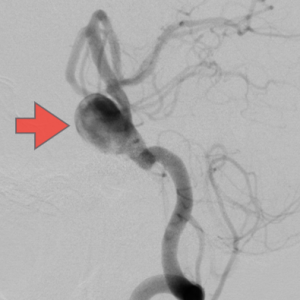

当科で治療した年々大きくなった大型脳底動脈瘤の3次元脳血管撮影像です。脳動脈瘤と周囲の血管の状態が非常によく分かるため、術前に十分な検討が可能でした。

正常の脳底動脈の血流は維持されている。